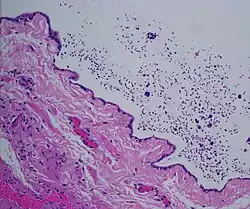

| Ultrasound of a testicle (grey) and a spermatocele (black). | |

Spermatocele is a fluid-filled cyst that develops in the epididymis.[3] The fluid is usually a clear or milky white color and may contain sperm.[4] Spermatoceles are typically filled with spermatozoa[5] and they can vary in size from several millimeters to many centimeters. Small spermatoceles are relatively common, occurring in an estimated 30 percent of males.[6] They are generally not painful. However, some people may experience discomfort such as a dull pain in the scrotum from larger spermatoceles.[7] They are not cancerous, nor do they cause an increased risk of testicular cancer. Additionally, unlike varicoceles, they do not reduce fertility.[7]

The primary care physician may diagnose and manage benign causes of scrotal masses such as hydrocele, varicocele and spermatocele. However, if a "must not miss" diagnosis related to testicular masses such as testicular torsion, epididymitis, acute orchitis, strangulated hernia and testicular cancer is suspected, the family physician must refer to a urologist.[19] Finding a painless, cystic mass at the head of the epididymis that is clearly separate from the testicle can indicate a spermatocele. Shining a light through the mass, a process known as transillumination, can also help differentiate between a fluid-filled cyst and a tumor, which would not allow as much light to pass.[20] If uncertainty exists, ultrasonography of the scrotum can confirm the presence of a spermatocele.[7] The location and history of any scrotal masses are crucial in determining whether or not the mass is benign or malignant.[21] Lab tests such as a complete blood count (CBC test) or urine test can also be conducted to check for any possible infection or signs of inflammation.[22]

Spermatoceles come in varying sizes and shapes. Some spermatoceles are very small and can only be detected through an ultrasound. More commonly seen are spermatoceles that are a pea-sized lump. They tend to form above or behind a testicle and have a shape and size that looks like a pea. Larger growths have been reported to look similar to a third testicle and can be very discomforting.[22] For those who are affected with large spermatoceles, some have reported feeling pain, heaviness, and fullness in the affected testicle.[20]